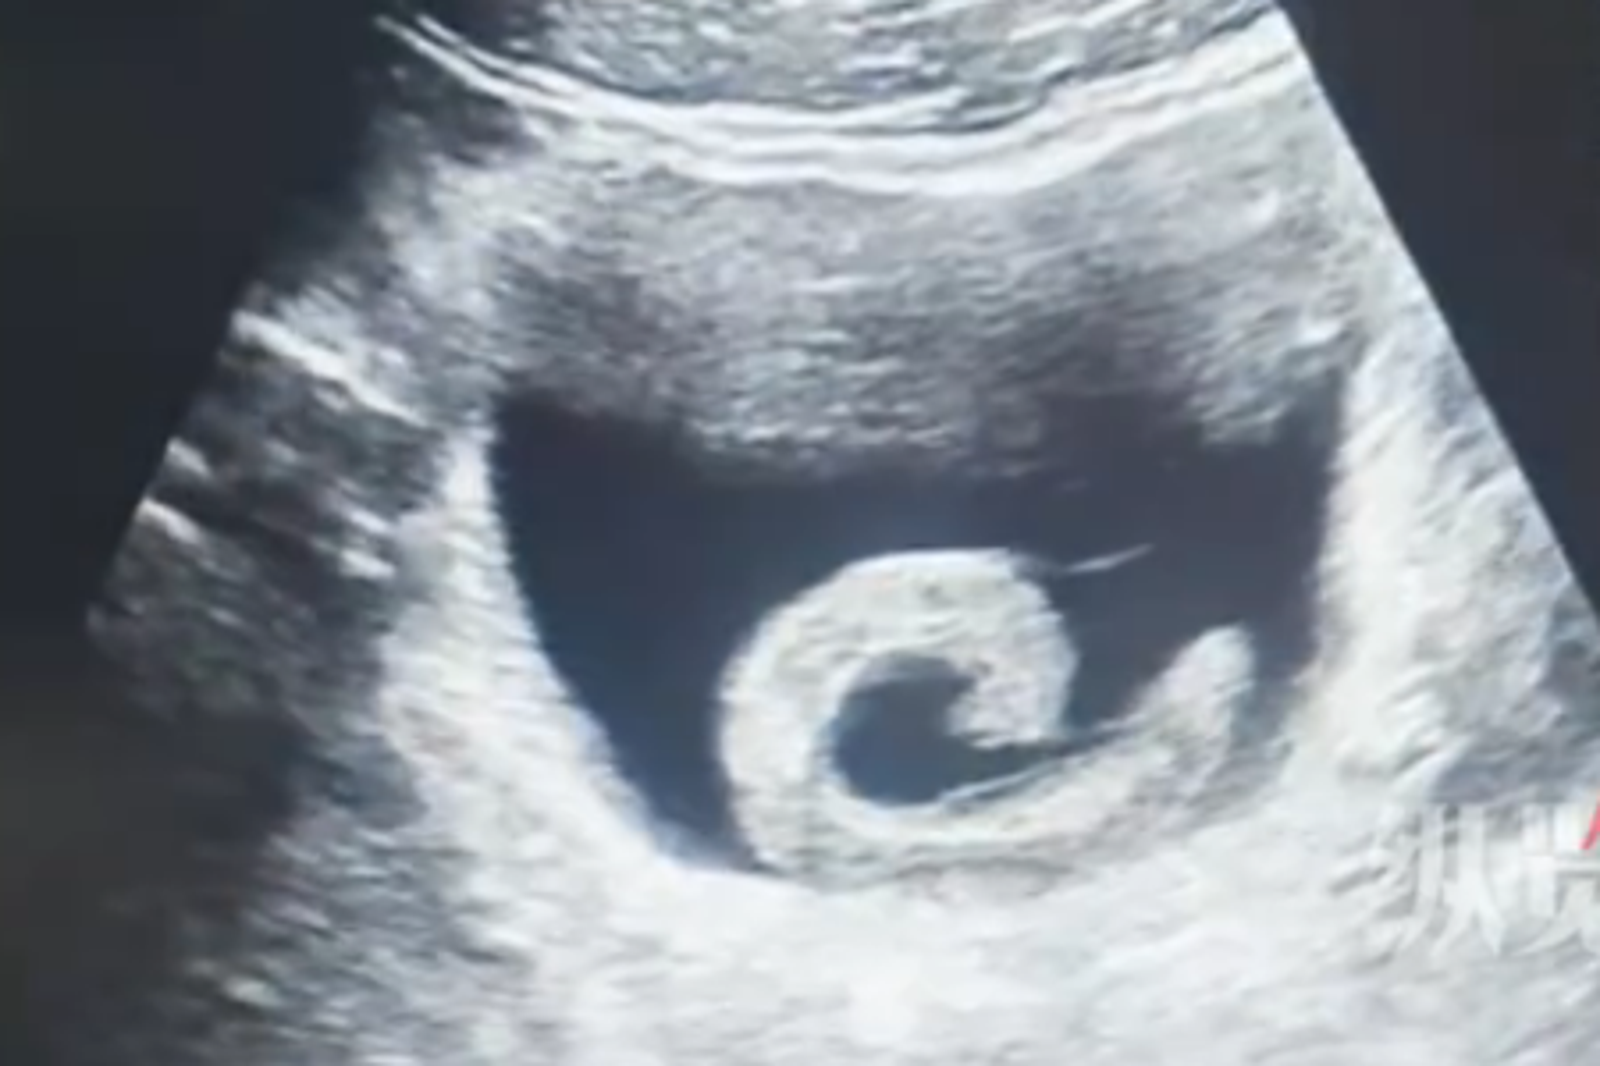

男子睡夢中感到劇烈疼痛,同時出現排尿困難,緊急前往醫院救治,醫師透過內視鏡檢查,發現水蛭長達5至6公分,而吸附膀胱的黏膜嚴重腫脹,經手術已經排除尿道阻塞疼痛問題;不過男子透過水蛭尋求「奇特」感受效果,他坦言當時相當害怕並後悔。